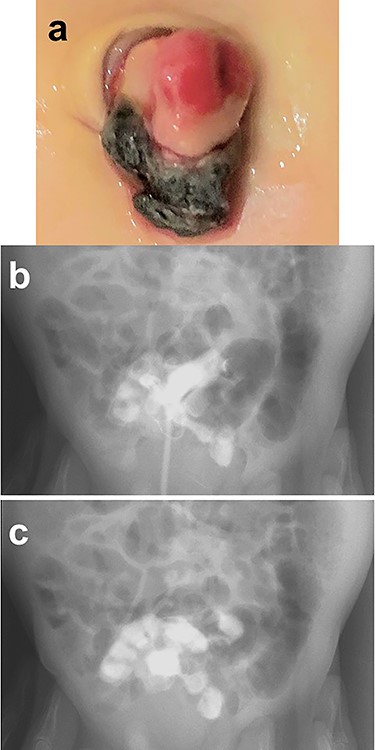

A male infant was born at 39 weeks of gestation, weighing 3036 g. His mother had been treated for Basedow’s disease. After the umbilical cord was ligated, there appeared to be a small stoma present at the base of the cord, with yellowish discharge (Fig. 1a). He was referred to our hospital at 22 days of age. We injected contrast media through a catheter inserted into the stoma and noted that contrast entered the lumen of the small bowel, establishing the diagnosis of a patent omphalomesenteric duct (Fig. 1b and c).

Physical findings on outpatient consultation and trans-stomal fistulography. (a) There appears to be a small stoma present after ligation of the umbilical cord. (b and c) Contrast media, injected through a catheter inserted into the stoma, enters the lumen of the small bowel.